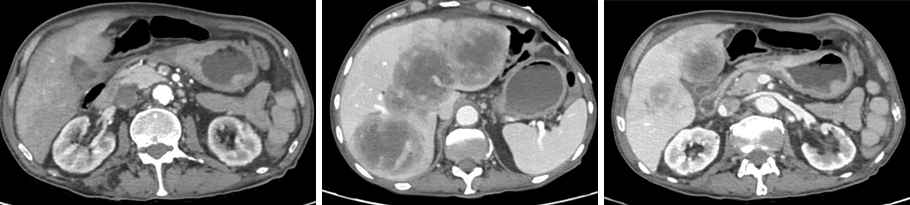

Dans ce contexte, vous lui organisez une gastroscopie rapidement et vous lui prescrivez un scanner thoraco-abdomino-pelvien dont voici les images.

Figure 3 (Élisabeth Capelle, La Revue du Praticien)

Question 7 - Sur le scanner, vous observez (une ou plusieurs réponses exactes) :

Il n’y a pas de dilatation du tube digestif, ni de jonction grêle plat-grêle dilaté.

On voit des métastases hépatiques mais le foie n’est pas à contours bosselés.

On voit une masse tissulaire qui fait saillie de la paroi (voir figure 4).

Il n’y a pas de liquide libre dans la cavité péritonéale.

La rate se rehausse bien, sans hypodensité.

Figure 4 (Élisabeth Capelle, La Revue du Praticien)